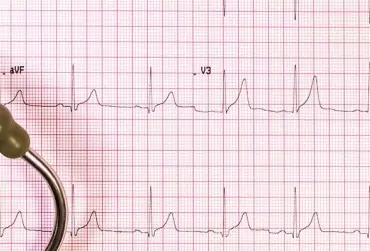

Rodzinnie występujący zespół wydłużonego QT. Opis przypadku

Wrodzony zespół wydłużonego QT (long QT syndrome) to pierwotna elektryczna choroba serca charakteryzująca się nieprawidłowym wydłużeniem, stale lub okresowo, odstępu QT w zapisie EKG oraz predyspozycją do występowania komorowych zaburzeń rytmu serca pod postacią wielokształtnego częstoskurczu komorowego oraz migotania komór. Zespół LQTS spowodowany jest mutacjami w kanałach jonowych w obrębie kardiomiocytów. Częstość występowania szacuje się na 1:5000 do 1:20 000 urodzeń. Rozpoznanie opiera się na podstawie wywiadu od pacjenta, wywiadu rodzinnego, zapisu EKG spoczynkowego oraz metodą Holtera. Leczenie standardowo rozpoczyna się od dużych dawek leków blokujących receptory beta- adrenergiczne.